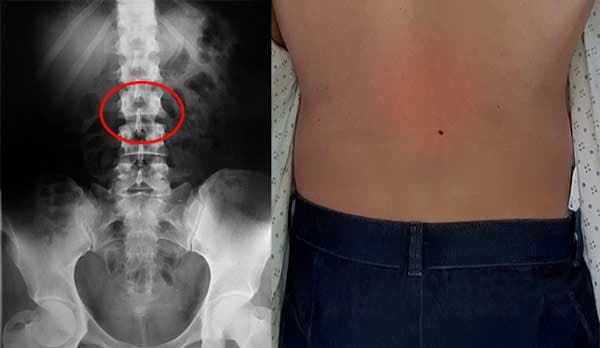

— Di tahap awal, penyakit sendi mungkin hanya muncul sebagai rasa tidak nyaman. Tapi rasa nyeri ringan di lutut itu bisa membuat Anda terbaring di tempat tidur suatu hari nanti. Tanpa perawatan yang tepat, rasa tidak nyaman, nyeri, atau bunyi "krek" bisa berkembang menjadi kondisi serius: kerusakan tulang rawan sendi, artritis, artrosis, osteoartritis, asam urat, bursitis, sinovitis, spondiloartritis, bahkan kelumpuhan sendi total. Yang terpenting — jangan menunda pengobatan! Penyakit sendi yang dibiarkan bisa menyebabkan disabilitas permanen.

Kerusakan mungkin sudah terjadi, meski belum terlihat jelas, dan hanya terasa sebagai nyeri ringan, rasa menusuk, atau bunyi gemeretak saat menggerakkan sendi.

Invanil adalah obat terbaik untuk artrosis! Saya menang diskon, walaupun dokter saya dulu gak rekomendasi produk ini. Tapi sekarang dia malah heran)) Dia sendiri lihat hasil rontgennya bagus. Saya akan lanjutkan pengobatan dan lihat apa kata dia nanti.

Pertama-tama, saya ingin ucapkan terima kasih kepada tim pembuat Invanil atas penemuan luar biasa ini! Jujur, awalnya saya skeptis, saya kira ini cuma “obat segala penyakit” biasa. Tapi setelah saya bisa hidup tanpa rasa sakit, saya cuma bisa bilang: terima kasih! Dalam sebulan saya lupa apa itu nyeri sendi. Saya bisa olahraga lagi! Dulu saya atlet lari profesional, tapi karena artrosis saya gak bisa jalan normal, apalagi lari! Sekarang saya merasa sehat sepenuhnya! Dan karena semua orang di sini bagikan foto, saya juga akan tunjukkan hasil saya.